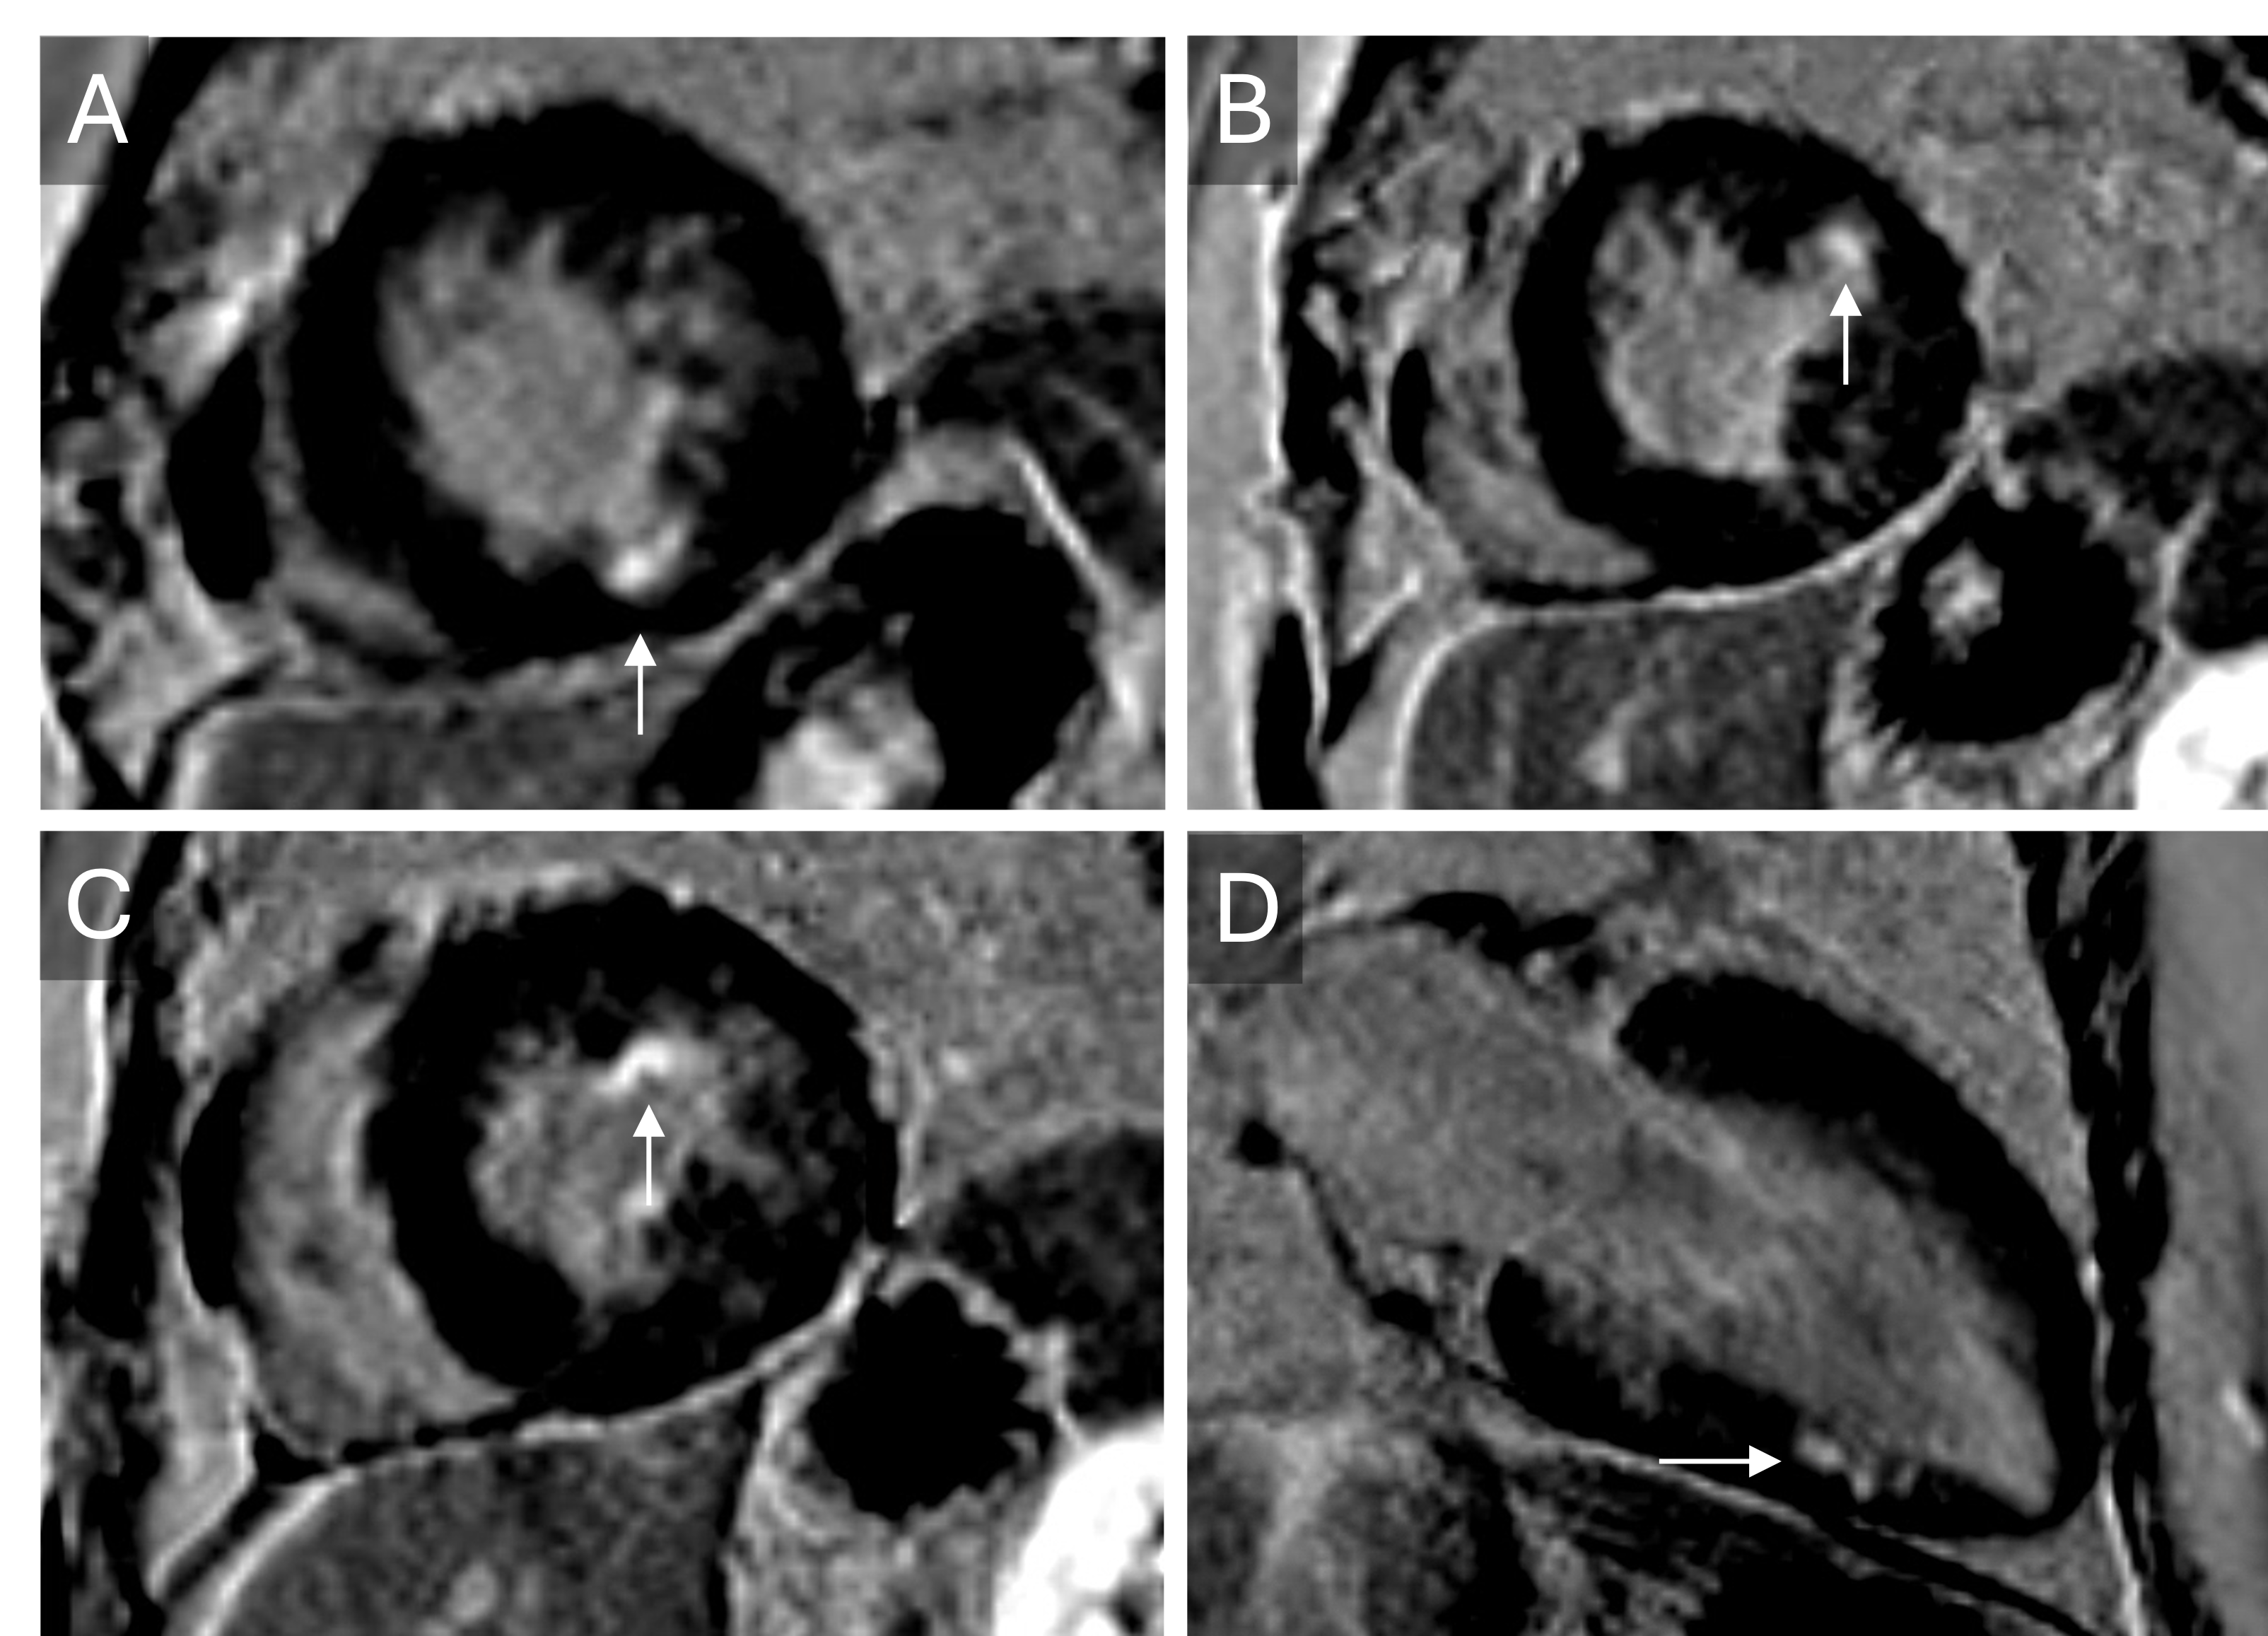

Thru-plane velocity flow mapping of the aortic valve showing aliasing at an encoding velocity of 3.25 m/s (A) that resolves at 4 m/s (B). In-plane velocity flow mapping in LVOT view (C) revealing aortic turbulence. The peak aortic velocity is estimated between 3.25 and 4.0 m/s, consistent with moderate stenosis.